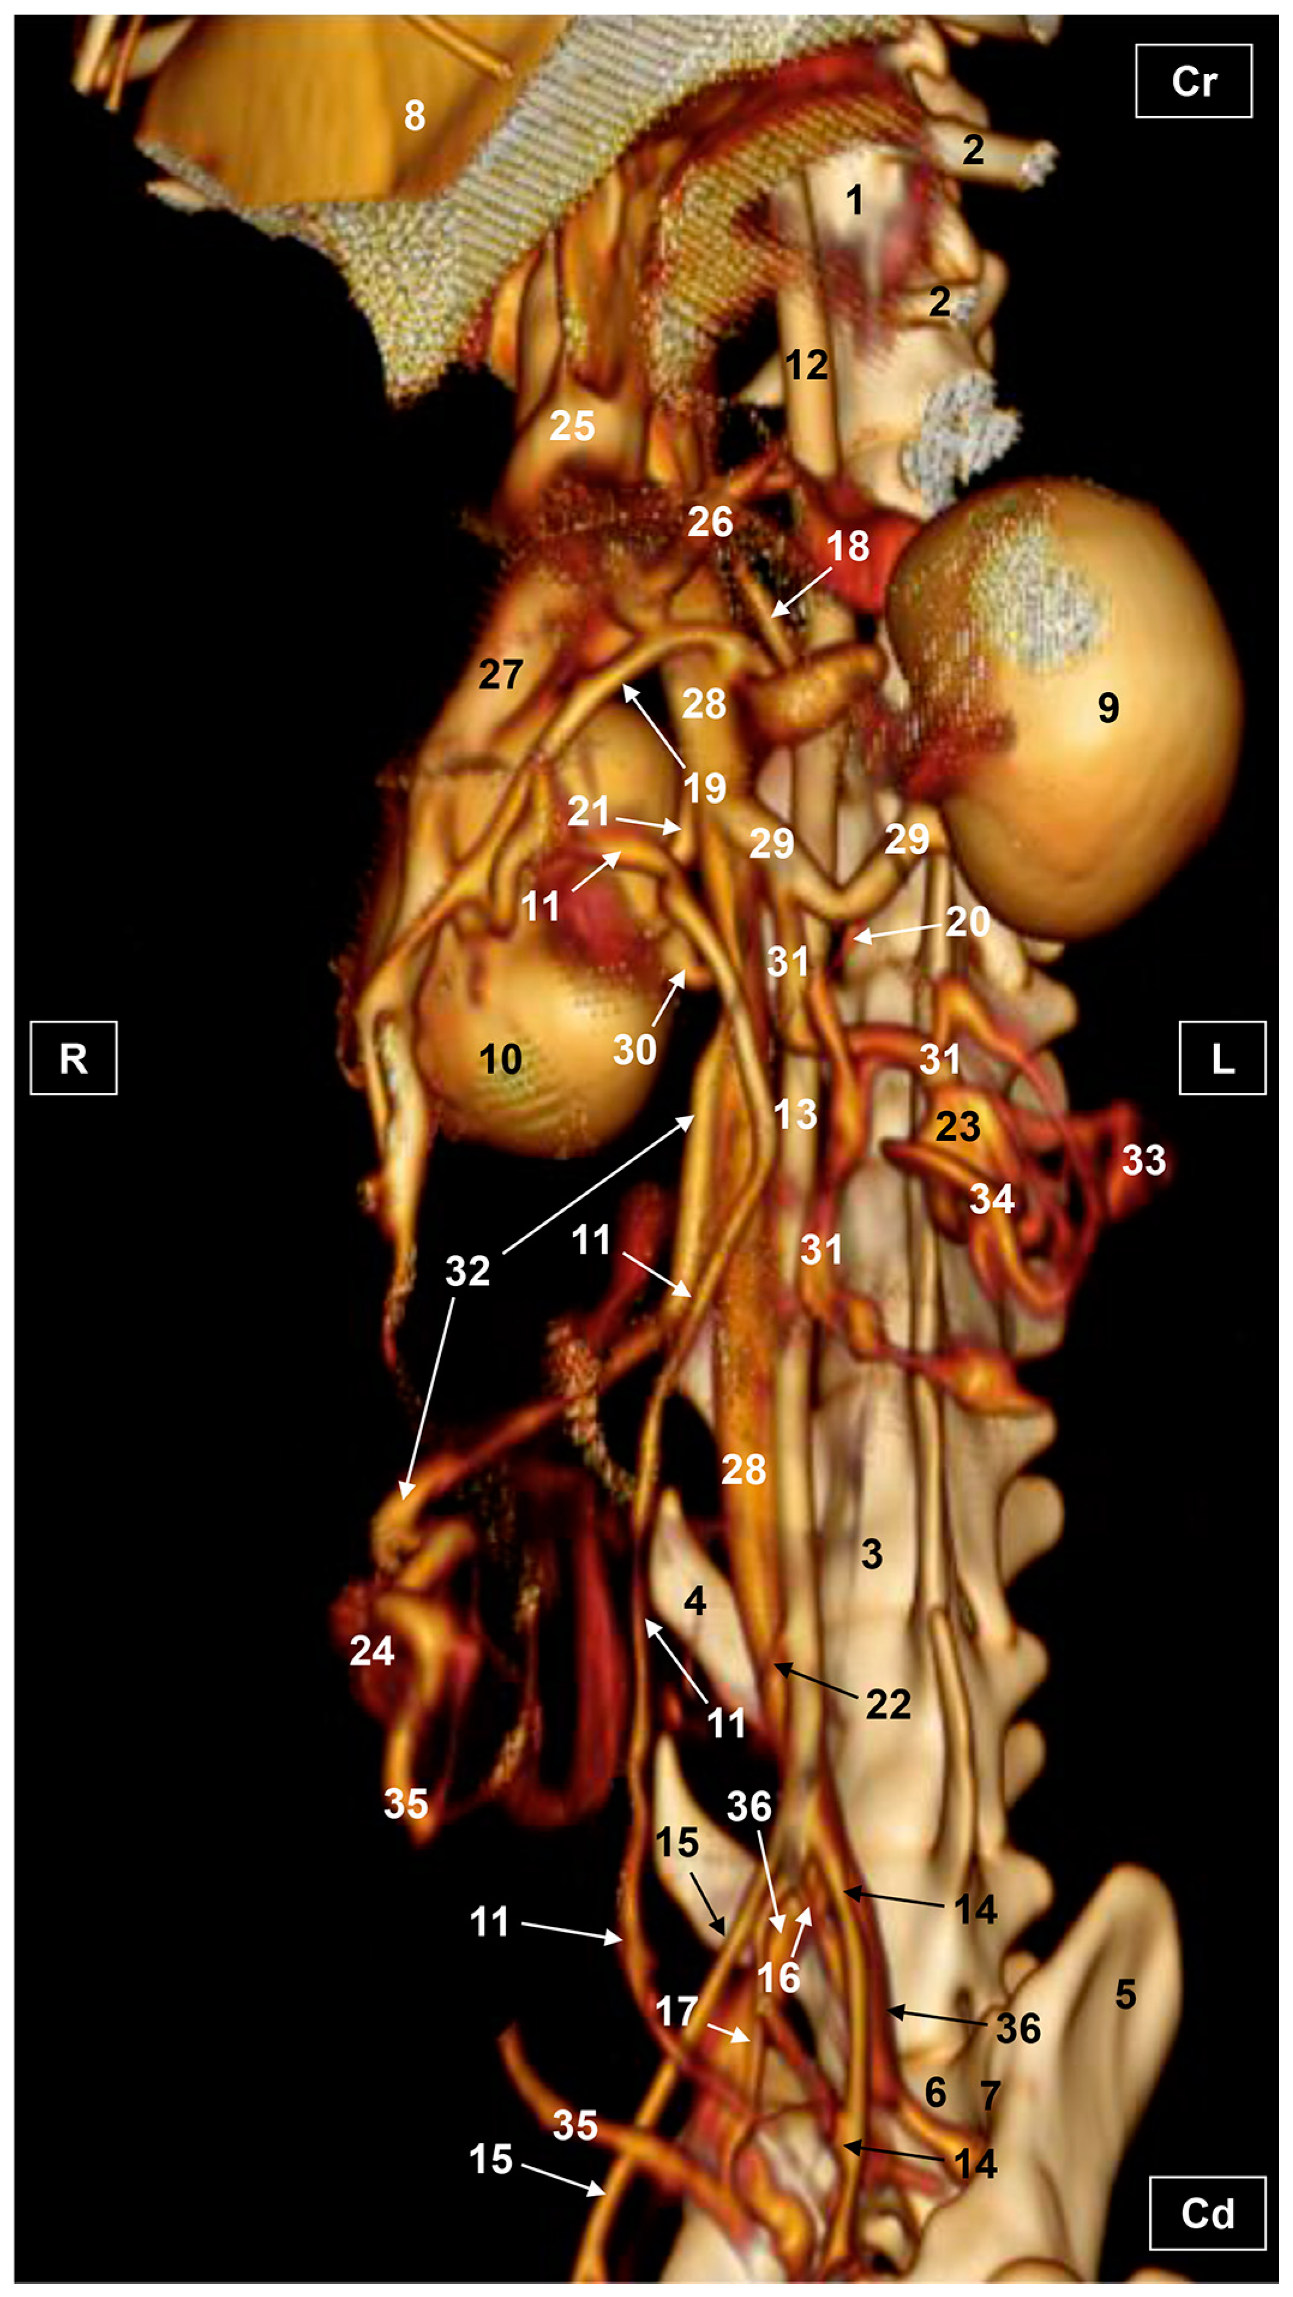

3.1. Gross Dissections

3.1.1. Arterial System

3.1.2. Venous System

3.2. Computed Tomography Angiography and 3D Printing

3.2.1. Arterial System

3.2.2. Venous System